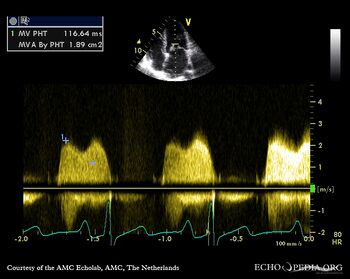

| Severe mitral valve stenosis

Continuous-wave Doppler signal of transmitral flow: PHT 117 msec